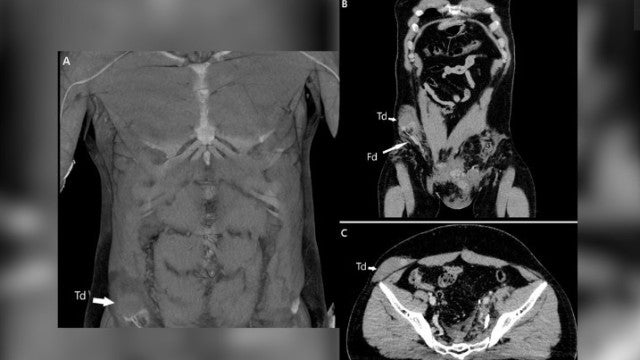

Só depois de uma tomografia computadorizada (TC) é que os médicos se aperceberam que o testículo tinha sofrido uma grande deslocação.

No caso agora reportado, os médicos demoraram um pouco para diagnosticar a luxação. O homem chegou às urgências com um grande hematoma no escroto, por isso os profissionais de saúde não conseguiram fazer logo o exame. Primeiro, eles tentaram controlar as hemorragias que poderiam levar à morte do homem, cuidaram das fraturas extensas que ele sofreu e tentaram perceber se algum órgão vital, como a bexiga, havia sido afetado.

De acordo com o relatório médico, o homem sofreu um impacto violento na virilha durante o acidente. O impacto empurrou o testículo direito do homem para fora do escroto, através do canal inguinal, uma pequena passagem que leva os testículos do abdômen para a bolsa escrotal.